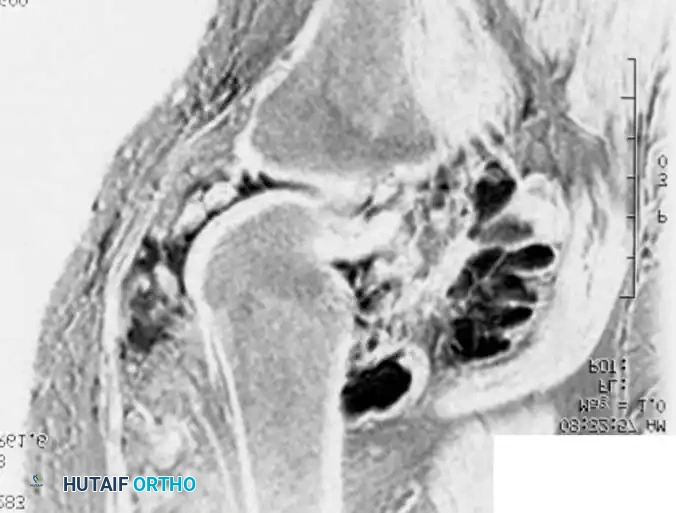

BENIGN TUMORS AND TUMOR-LIKE LESIONS Surgical Diagram

Radiograph and MRI of a shoulder with synovial chondromatosis, demonstrating multiple intra-articular ossified loose bodies. The gross specimen photograph highlights the sheer volume of cartilaginous bodies resected during synovectomy.